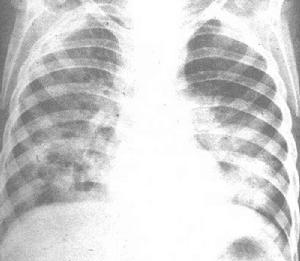

(1)肺間質纖維化胸部X 線檢查:可發現雙下肺網狀及結節狀密度增高陰影,病變嚴重時可累及雙側全肺,少數病例胸部平片可以正常。肺功能檢查可呈不同程度的限制性通氣功能障礙和彌散功能降低。肺組織病理檢查可見非典型Ⅱ型肺泡上皮細胞增生、肺泡炎或肺間質炎症以及不同程度的肺間質纖維化。